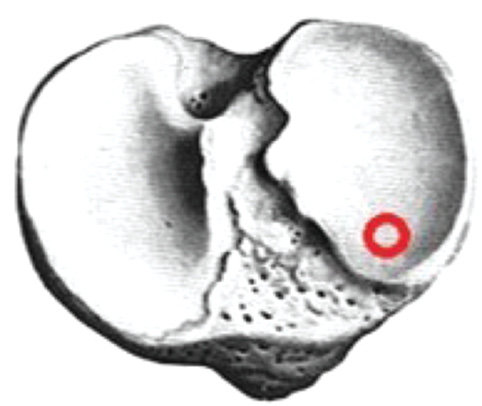

If the primary channel was located anteriorly or posteriorly (Fig. 3), a standard channel in the tibial bone was performed. When making a channel of a larger diameter, the graft was centered in the channel using Milagro screws (DePuy Mitek, USA).

Fig. 3. Variants of the location of the tibial canals, — correct channel placement.